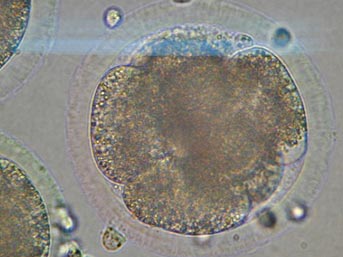

Zavos ayrıca, 10 yaşında trafik kazasında yaşamını yitiren Cady adlı bir kız çocuğu dahil olmak üzere, ölmüş 3 kişiden kopyalanmış embriyonlar ürettiğini, bunu, yaslı ailelerin, sevdikleri kişilerin biyolojik kopyalarını yaratıp yaratamayacağını sormaları üzerine yaptığını açıkladı.